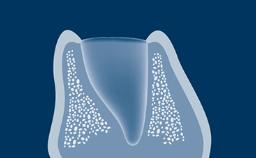

Os pacientes necessitam de tratamento com implantes dentários frequentemente após um evento que causou a extração de um dente ou após um evento traumático que levou à perda do dente. Na maioria dos cenários, o osso alveolar será submetido a reabsorção na região do implante planejado. Considerando que os implantes devem sempre ser instalados em uma posição protética tridimensional ideal, os defeitos peri-implantes nos ossos e tecidos moles são frequentemente encontrados quando os implantes são instalados. Se esses defeitos forem pequenos, eles podem ser tratados no momento da instalação do implante com um alto grau de previsibilidade. Se os defeitos forem grandes, é preferida uma abordagem em etapas, na qual o aumento é realizado primeiro e o implante instalado posteriormente. Este módulo tratará do manejo de defeitos dos tecidos duros e moles peri-implantares resultantes de alterações teciduais pós-extração.